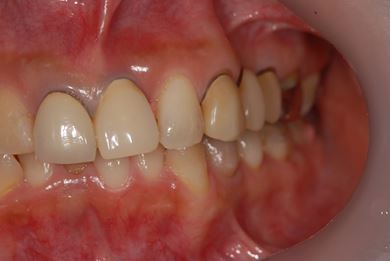

| 性別/年齢 | 女性 / 40歳 | ||||||||||||||||||||||||||||||||

| 主訴 | 前歯のさし歯の部分が目立ってしまい、新しくしたい。痛みも少しある。 | ||||||||||||||||||||||||||||||||

| 治療方針 | 保存不能な歯を抜歯し、セラミック治療にて、機能的・審美的回復を行う。 | ||||||||||||||||||||||||||||||||

| 治療内容 | ジルコニアフレームオールセラミッククラウン7本(オールセラミック用土台3本)、ハイブリッドセラミッククラウン1本、ハイブリッドセラミックインレー1本 | ||||||||||||||||||||||||||||||||